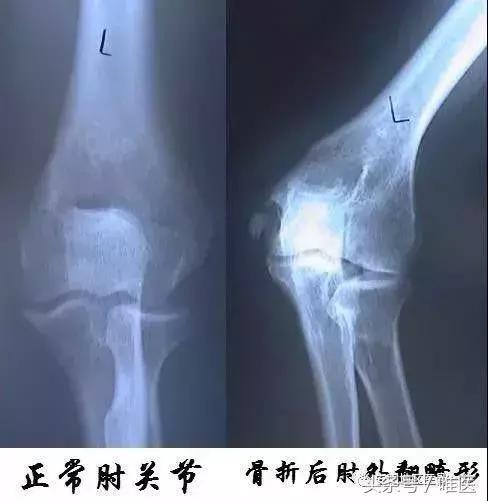

其次是肘部急性損傷,肱骨遠端骨折、肘關節脫位等可引起尺神經急性或繼發受壓;

還有先天或後天性肘外翻、或肘管內發生腫瘤,尺神經被壓而產生一系列症狀。